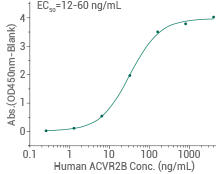

Human ACVR2B protein

Immobilized Human, Mouse, Rat, Cynomolgus, Rhesus Activin A (Cat#: 10429-HNAH) can bind Human ACVR2B. Image Credit: Sino Biological Inc.